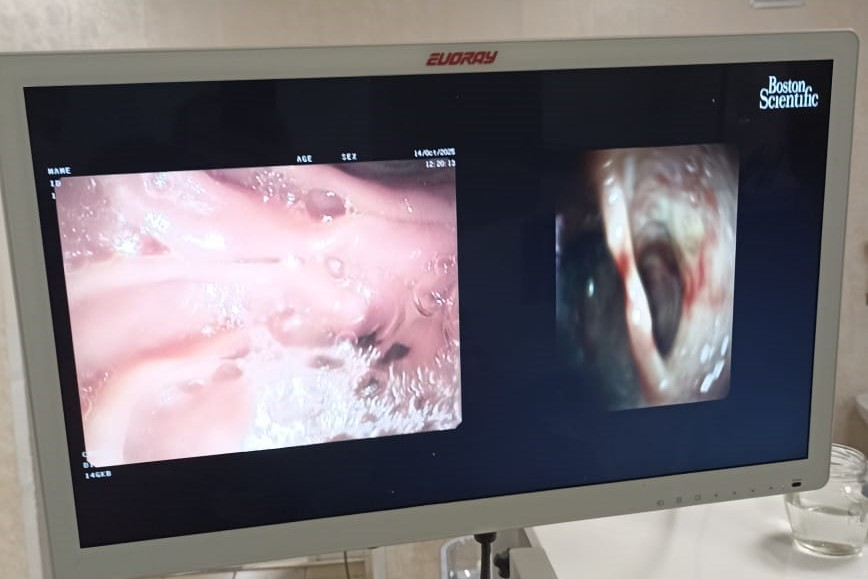

Бригада медиков провела операцию в два этапа. Сначала был обеспечен доступ к желчным протокам, затем с помощью холедохоскопа SpyGlass проведена холангиоскопия и выполнена контактная лазерная литотрипсия конкрементов с удалением осколков.

«Технология SpyGlass открывает новые возможности в лечении пациентов с высокой степенью операционного риска. Это пример того, как современное медицинское оборудование позволяет выполнять хирургические вмешательства у пациентов со сложным холедохолитиазом и с высокой степенью через естественные пути, минимизируя травматизм, боль и сроки восстановления. Мы надеемся активно развивать это направление в нашей больнице», — подчеркнул специалист учреждения здравоохранения.

Добавим, что SpyGlass (дословно «подзорная труба») — это ультратонкий эндоскоп, который проводится в желчные протоки через канал операционного дуоденоскопа, введённого в просвет двенадцатиперстной кишки. Технология обеспечивает прямой визуальный контроль, превращая диагностику в лечебную процедуру. Врач видит желчные протоки изнутри в высоком качестве, далее также под визуальным контролем крупные камни дробятся лазером на мелкие фрагменты, которые извлекаются наружу. Визуализация просвета желчных протоков позволяет также прицельно забирать образцы тканей для исследования при подозрении на опухоль.